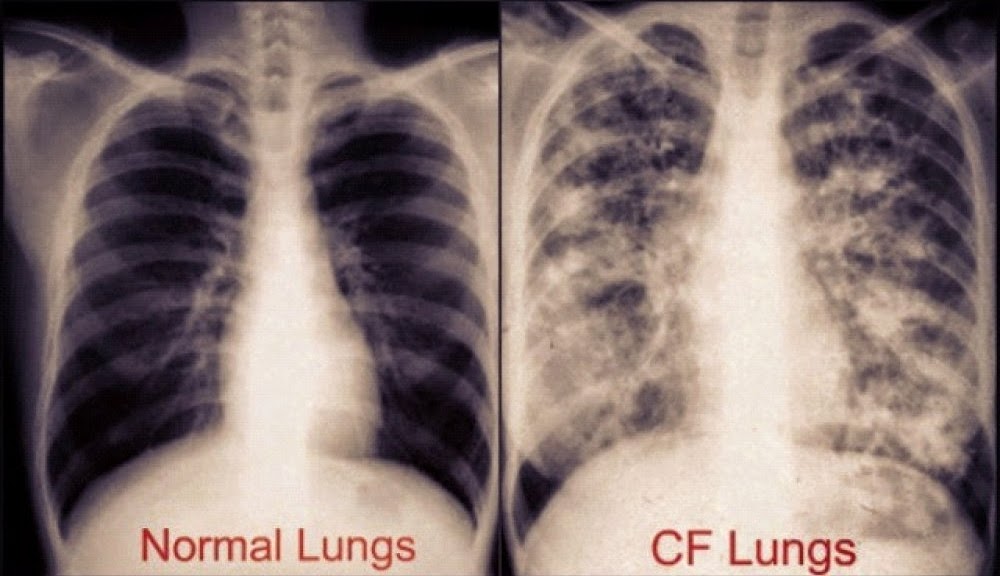

Για παράδειγμα, στους πνεύμονες η βλέννα αποφράσσει τους αεραγωγούς, με συνέπεια συχνές μικροβιακές λοιμώξεις και ανοσολογικές αντιδράσεις που οδηγούν στην έκκριση περισσότερης βλέννας, η οποία ευνοεί με τη σειρά της την εγκατάσταση μικροβίων, δημιουργώντας έτσι ένα φαύλο κύκλο. Στο πάγκρεας παρεμποδίζεται η παραγωγή ενζύμων απαραίτητων για την πέψη των τροφών. Οι ιδρωτοποιοί αδένες παράγουν πολύ αλμυρό ιδρώτα, γεγονός που δημιουργεί σοβαρούς κινδύνους αφυδάτωσης, αλλά ταυτόχρονα βοηθάει στην ασφαλή διάγνωση της νόσου μέσω του τεστ ιδρώτα.

Κυστική ίνωση: Συμπτώματα στο αναπνευστικό σύστημα

Επίμονος βήχας που παράγει παχύρρευστη (πτύελα) βλέννα

Συριγμός

Δύσπνοια

Δυσανεξία στην άσκηση

Επαναλαμβανόμενες λοιμώξεις των πνευμόνων

Φλεγμονή στις ρινικές διόδους ή βουλωμένη μύτη

Πώς φαίνεται η κυστική ίνωση (Cystic Fibrosis – CF) στην ακτινογραφία: